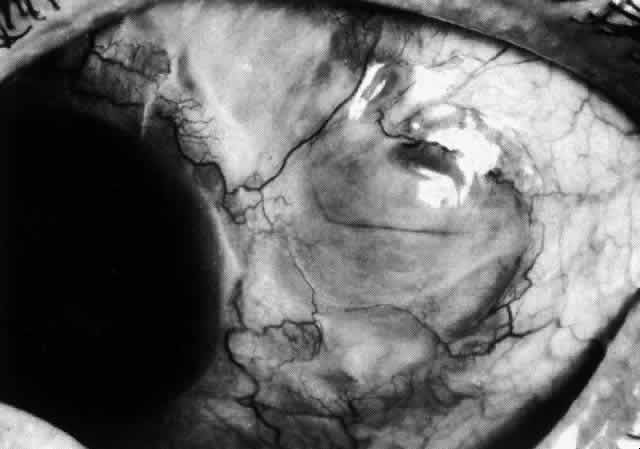

The sclera that is edematous is pushed forward, and the deep episcleral network is more congested than the superficial networks (Figs. 27 and 28). It is usually easy to ascertain by simple observation that the patient has scleritis and not episcleritis. However, it is not as easy to ascertain whether the patient has early necrotizing scleritis. It is in these patients that fluorescein angiography has considerable value, because the first changes are detectable in the ocular vasculature. Prompt and adequate treatment can prevent these changes from becoming irreversible.

Fig. 27. In scleritis, maximum congestion occurs in deep episcleral plexus, which is bowed forward by underlying scleral edema. Episcleral tissue is slightly infiltrated and superficial plexus is slightly congested (see Fig. 14). (Watson PG, Hayreh S, Awdry P: Episcleritis and scleritis. Br J Ophthalmol 52:278–279, 1968)

Fig. 28. Nodular scleritis. Both the anterior conjunctival slit and the deep scleral slit are displaced forward by the scleral edema. There is little separation between these two beams, indicating that all the edema is in the sclera and not in the overlying episclera. (Watson PG, Hayreh S, Awdry P: Episcleritis and scleritis. Br J Ophthalmol 52:278–279, 1968)

Diffuse Anterior Scleritis

Diffuse anterior scleritis is the most common and least severe type of scleritis. The inflammation is widespread, and it may involve either a small segment or the whole of the anterior segment, sometimes with such severe overlying inflammation as to justify the name “brawny” scleritis (Fig. 29). On slit lamp examination, the vascular pattern of both deep and superficial layers may be distorted, so that the normal radial pattern of the vessels is lost; large anastomotic channels develop, leading to beading and tortuosity of the remaining vessels (Figs. 30 and 31; Color Plate 1C).

Fig. 34. Scleral edema has displaced all the vessel layers forward. Area surrounding the nodule is acutely inflamed.

Fig. 35. Multiple scleral nodules. Surrounding inflammation is deep and intense. (Watson PG: Management of scleritis. In: Recent Advances in Ophthalmology, Vol 5. London, Churchill-Livingstone, 1975)